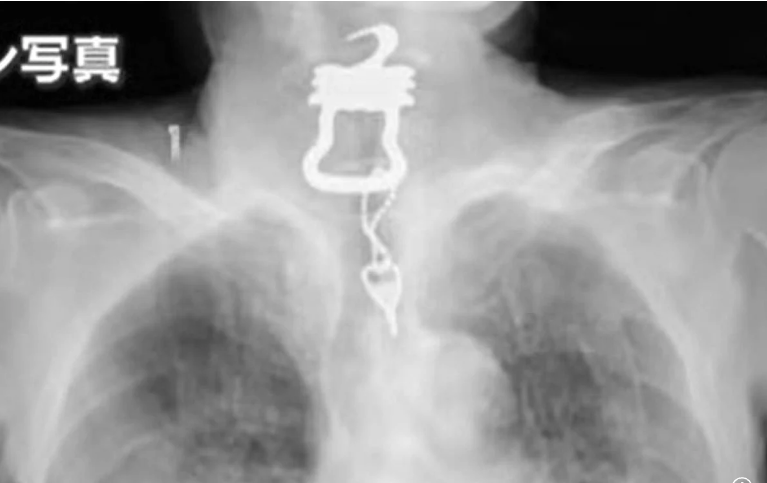

دعوى قضائية ضد مستشفى بعدما ابتلع أحد المرضى مفتاحا وتوفي